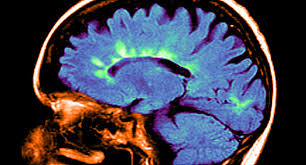

Multiple sclerosis (ms) is a potentially disabling disease of the brain and spinal cord (central nervous system). What research is being done? Multiple sclerosis (ms) symptoms, causes, treatment, life expectancy. In ms , the immune system attacks the protective sheath (myelin) that covers nerve fibers. This can lead to a wide range of symptoms throughout the body.

Multiple sclerosis (ms) is a chronic inflammatory, demyelinating, and neurodegenerative disorder of the central nervous system (cns) that affects the white and grey matter of the brain, spinal cord, and.

Multiple sclerosis (abbreviated ms, known as disseminated sclerosis or encephalomyelitis disseminata) is an inflammatory disease in which the fatty myelin sheaths around the axons of the. Multiple sclerosis (ms) is a chronic autoimmune debilitating disease in which nerve damage (demyelination of neurons) in the brain and spinal cord disrupts their communication with the body. Multiple sclerosis information including symptoms, diagnosis, treatment, causes, videos, forums, and local community support. Find answers to health issues you can trust from healthgrades.com. Ms causes gradual destruction of myelin (demyelination) and breakdown of neuronal axons throughout the brain and spinal cord.